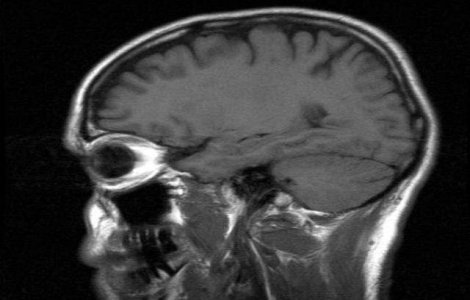

Infectia cu virusul Herpex simplex de tip 1, care cauzeaza leziuni in zona gurii, mai ales pe buze, este foarte comuna, circa 90% dintre adulti fiind purtatori.

Oamenii de stiinta au demonstrat ca un copil din 10.000 prezinta convulsii febrile in urma unui vaccin combinat ROR (rujeola, oreion, rubeola).